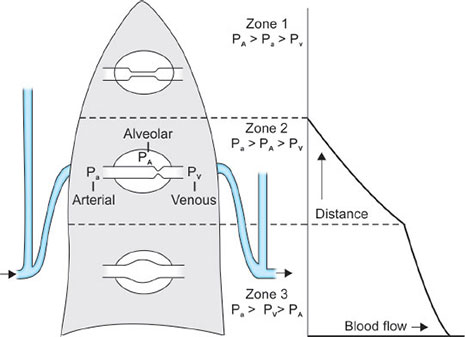

Distribution of Blood Flow

Blood flow within the lung is mainly gravity-dependent. Since the alveolar-capillary beds are not composed of rigid vessels, the pressure of the surrounding tissues can influence the resistance to flow through the individual capillaries. Thus, blood flow depends on the relationship between pulmonary artery pressure (Ppa), alveolar pressure (PA), and pulmonary venous pressure. West et al. and West and Dollery created a lung model which divides the lung into three zones (Fig. 30).

Zone 1 conditions occur in the most gravity-independent part of the lung (alveolar pressure is approximately equal to atmospheric pressure; and pulmonary artery pressure).

Zone 2 occurs from the lower limit of zone 1 to the upper limit of zone 3 = Ppa > Pα > Ppv. The pressure difference between pulmonary artery and alveolar pressure determines blood flow in zone 2. Pulmonary venous pressure has little influence. Well-matched ventilation and perfusion occur in zone 2, which contains the majority of alveoli (Figs. 30 and 31).

Zone 3 occurs in the most gravity-dependent areas of the lung = Ppa > Ppv > PA. blood flow is primarily governed by the pulmonary arterial to venous pressure difference. Because gravity also increases pulmonary venous pressure, the pulmonary capillaries become distended. Thus, perfusion in zone 3 is lush, resulting in capillary perfusion in excess of ventilation, or physiologic shunt.

Schematic representation of the effects of gravity on the distribution of pulmonary blood flow in the lateral decubitus position. Vertical gradients in the lateral decubitus position are similar to those in the upright position and cause the creation of West zones 1, 2, and 3. Consequently, pulmonary blood flow increases with lung dependency, and is largest in the dependent lung and least in the nondependent lung. Pa, pulmonary artery pressure; PA, alveolar pressure; Pv, pulmonary venous pressure.